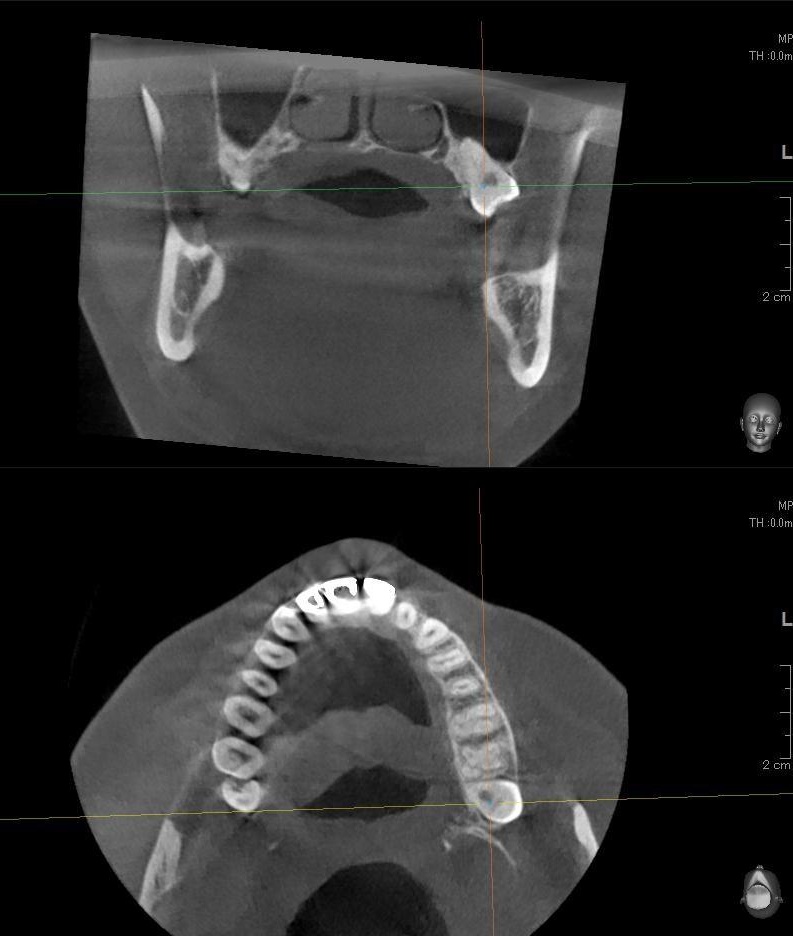

さらに、上顎の親知らずは上顎洞(副鼻腔)に近接して生えている場合もあるため、CTを撮影して位置関係を詳しく解析します。

上顎の親知らずが上顎洞(副鼻腔)に近い位置に生えている場合や、上顎洞へ突き抜けている可能性がある場合は、大きな病院に紹介する場合もあります。

今回は上顎洞からも距離があるため、抜歯は可能と診断されました。